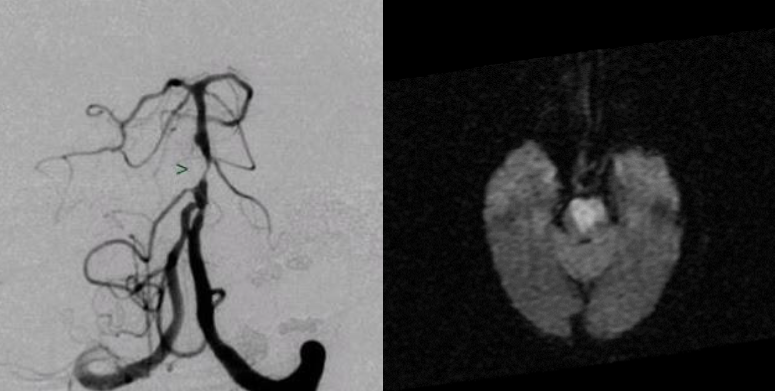

What is the best type of imaging for Vertebrobasilar insufficiency?

Vascular imaging

What does Mr. Smith have?

Cerebellar lesion/stroke/hemorrhage/tumor/trauma